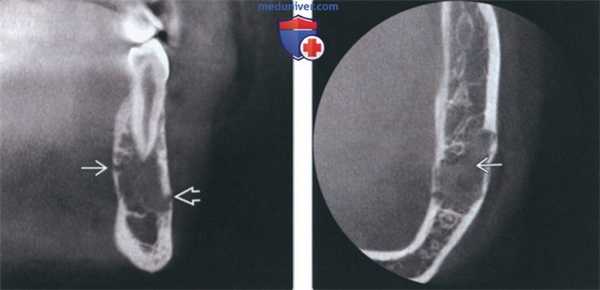

(Слева) На КЛКТ(профильный срез) у этой же пациентки структура ОБ выглядит зернистой. Обратите внимание на поражение язычной и щечной кортикальных пластинок в отсутствие вздутия.

(Справа) На аксиальной КЛКТ у этой же пациентки определяется поражение кортикальных пластинок опухолью с однородной зернистой структурой. ОБ челюстей обнаруживаются преимущественно в теле нижней челюсти; их рентгеновская плотность варьирует (рентенонегативное образование-опухоль смешанной плотности с множественными кальцинатами).

3. КТ при остеобластоме челюсти:

• КЛКТ и КТ в костном окне:

о Может обнаруживаться вздутие